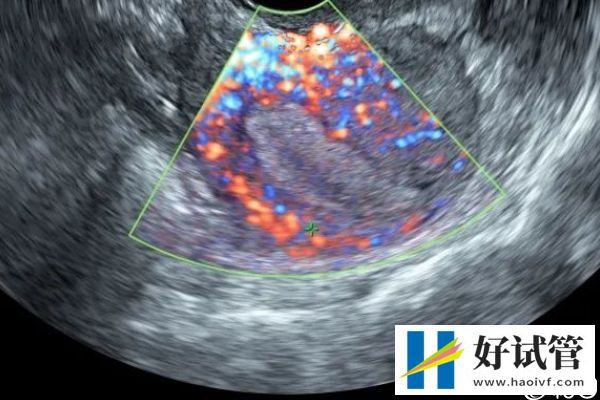

女性在胚胎移植前做针灸埋线可以帮助胚胎着床,也有一定的保胎作用,但是效果因人而异。针灸埋线是指通过穴位经脉沟通,有调整脏腑、平衡阴阳、调和气血的作用,增加试管移植的成功率,能增长内膜,调节体内内分泌。

移植前针灸能增长内膜

另外,针灸埋线温宫散寒,可以改善子宫附件的血供,适合宫寒的女性,经过调理,使宫内环境更适于胚胎着床。对于部分女性来说,胚胎移植前做针灸埋线还能改善子宫内膜状态,增加子宫内膜的容受性。